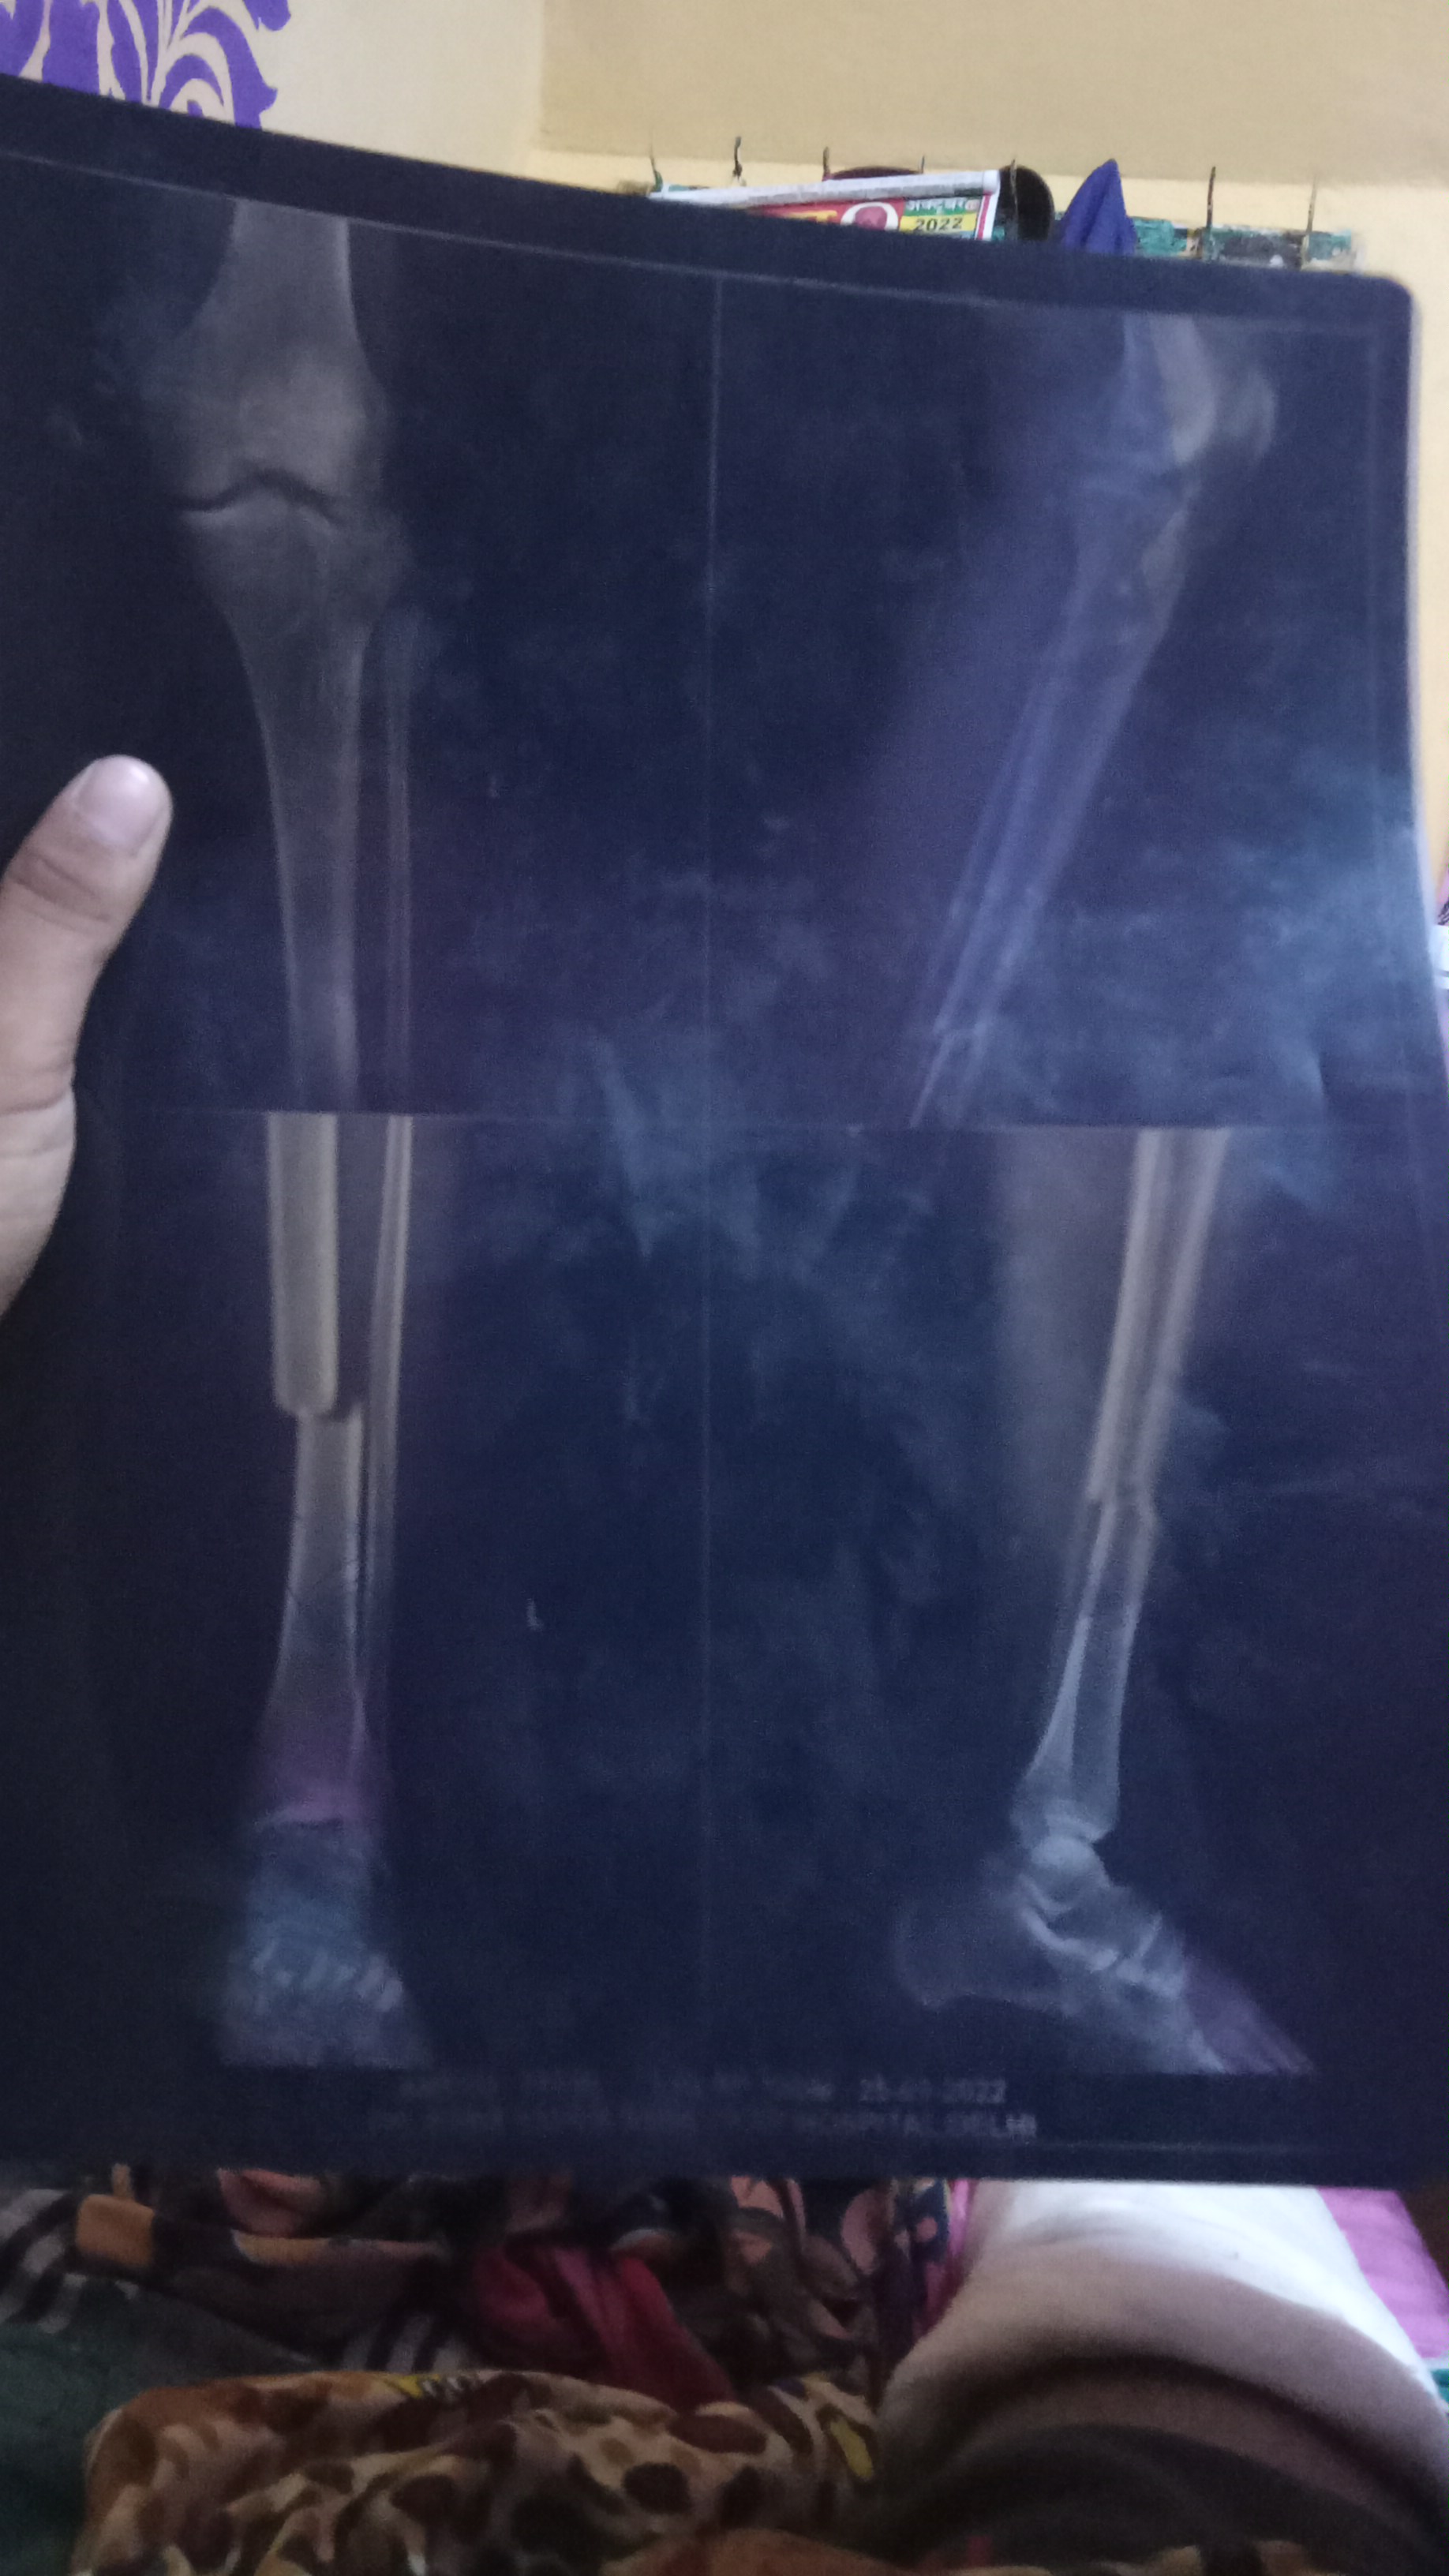

Dear sir 4.5 mahine ke baad dr. Ab kah raha hai ki isme haddi ka burada dalega dusre dr. Bhi ye kah rahe ki kulhe ki haddi nikal kar isme dalni padhegi ya phir ye jo febula bone judh gayi hai isko dobara broke karna padhega aur tibia bone ka dobara treatment karna padhega 2 solution bata rahe hai kya ye plate haddi ko nahi judhne de rahi ya koi aur baat hai febula to judh gayi tibia ka kya kiya jaye ya phir ye tablet khane se thik ho jayegi

Sir ji bone grafting ke alawa koi dusra upay DR. Ka kahna hai ki isme rod bhi nahi dhal rahi hai

isme bone grafting karna accha option hai aur plate judne se rok rahee hai . ho sakta hai plate ko bhee change karna pade